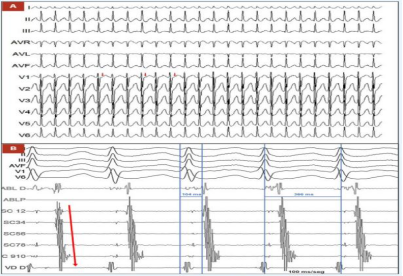

为精准定位心律失常病灶,心内科团队决定行心内电生理检查,具体操作如下:导管放置:在冠状窦(CS)放置十极导管,右心室(RV)放置四极导管,以记录心腔内电活动;心动过速诱发:检查期间成功诱发出临床症状相关的心动过速,表现为QRS波群窄(排除室性心动过速),周期长度为366ms。关键电生理特征:偏心性逆行心房激活(提示激动并非通过房室结逆传,而是存在旁路),VA 间期(心室到心房的传导时间)为104ms,符合左隐匿性旁路介导的顺向型房室折返性心动过速诊断(图 2A、2B)。

(图2A,图2B)

这一诊断至关重要-与常见的心房颤动介导的慢-快综合征不同,该患者的快速性心律失常由明确的 “隐匿性旁路” 引起,而非窦房结本身的原发性严重病变,这为 “消融术优先” 的治疗方案提供了依据。